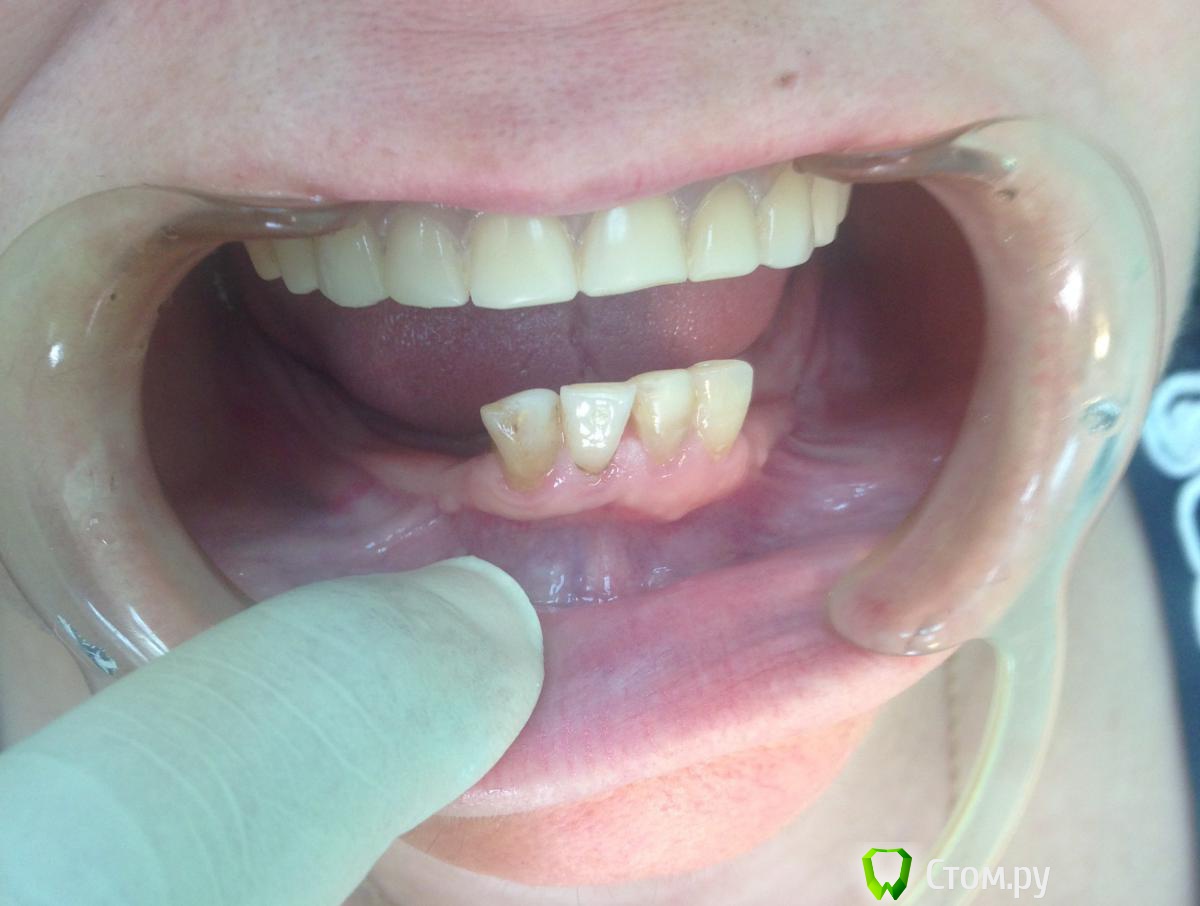

Фарид Расулыч Опубликовано 19 июня, 2014 Поделиться Опубликовано 19 июня, 2014 Добрый день. Обратилась пациентка 52 года. Настаивает на имплантации, изначально хотели тотальную имплантацию нижней челюсти, но, после взгляда на ОПТГ этот вариант отпал. Высота кости до нижнечелюстного нерва (~ 0,5 см, ширина альвеолярного отростка "пальпаторно" 1 см.) На данный момент мне в голову приходит только один вариант: удаление четырех нижних резцов, 2 импланта, один в область 42, второй в область 33. Полный съемный протез на лок абатментах. Кто что думает по этому поводу? или есть альтернативы? п.с. Качество ОПТГ удручающее.... Ссылка на комментарий